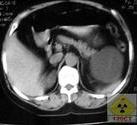

5、CT掃描:鑑別腎囊腫與腫瘤,CT是最精確的。囊液密度近似於水,而腫瘤的密度則與正常腎實質相近。靜脈注射造影劑後,腎實質變得更為濃密,而囊腫仍不受影響;囊腫壁與腎實質有明顯界限,而腫瘤則無;囊腫壁很薄,腫瘤卻不然。從許多方面來說,鑑別囊腫和腫瘤CT要優於穿刺抽液判斷。